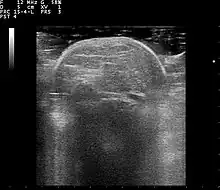

Familial multiple lipomatosis is usually diagnosed through a physical exam via palpation, medical history and imaging studies such as ultrasound, CT scan, or magnetic resonance imaging (MRI). A CT scan is an imaging method that uses x-rays to create images of cross sections of the body, while an MRI uses powerful magnets and radio waves to create images of lipomas and surrounding tissues.[3] Both tests are useful to establish the diagnosis of multiple symmetric lipomatosis, although magnetic resonance imaging provides more details and may be used when lipomas are large, deep, or have infiltrated muscle fibers or nerves. In some cases, a biopsy of the lipomas may be necessary to confirm the diagnosis.[3]